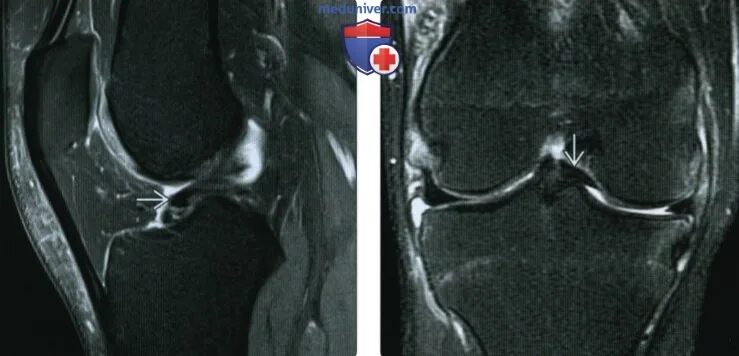

Повреждение рога латерального мениска